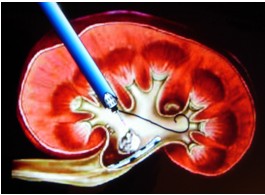

经皮肾镜下超声气压弹道混合动力碎石术:该项技术近年来发展较快,是肾脏及输尿管上段复杂结石治疗的一次革命,该技术避免患者腰部的大切口,仅需做一个肾穿刺造瘘,将肾镜引入肾内,直视下击碎结石,并将其吸出体外。其优点:创伤小,痛苦少,结石清除干净,具有可重复性。